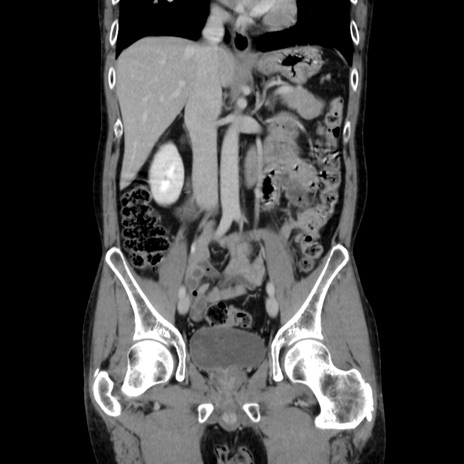

症例37(冠状断像)

【症例】40歳代 男性

【主訴】腹痛

【現病歴】4時間ほど前に電車に乗車中に臍部上より腹痛出現。徐々に増悪し起立困難となり、救急外来受診。生ものは数日食べていない。今朝お雑煮を食べた。

【身体所見】BT 36.8℃、BP 117/84mmHg、HR 91/min、SpO2 97%、苦悶様、腹部:臍上部広範囲圧痛あり、反跳痛±

【データ】WBC 8100、CRP 0.03